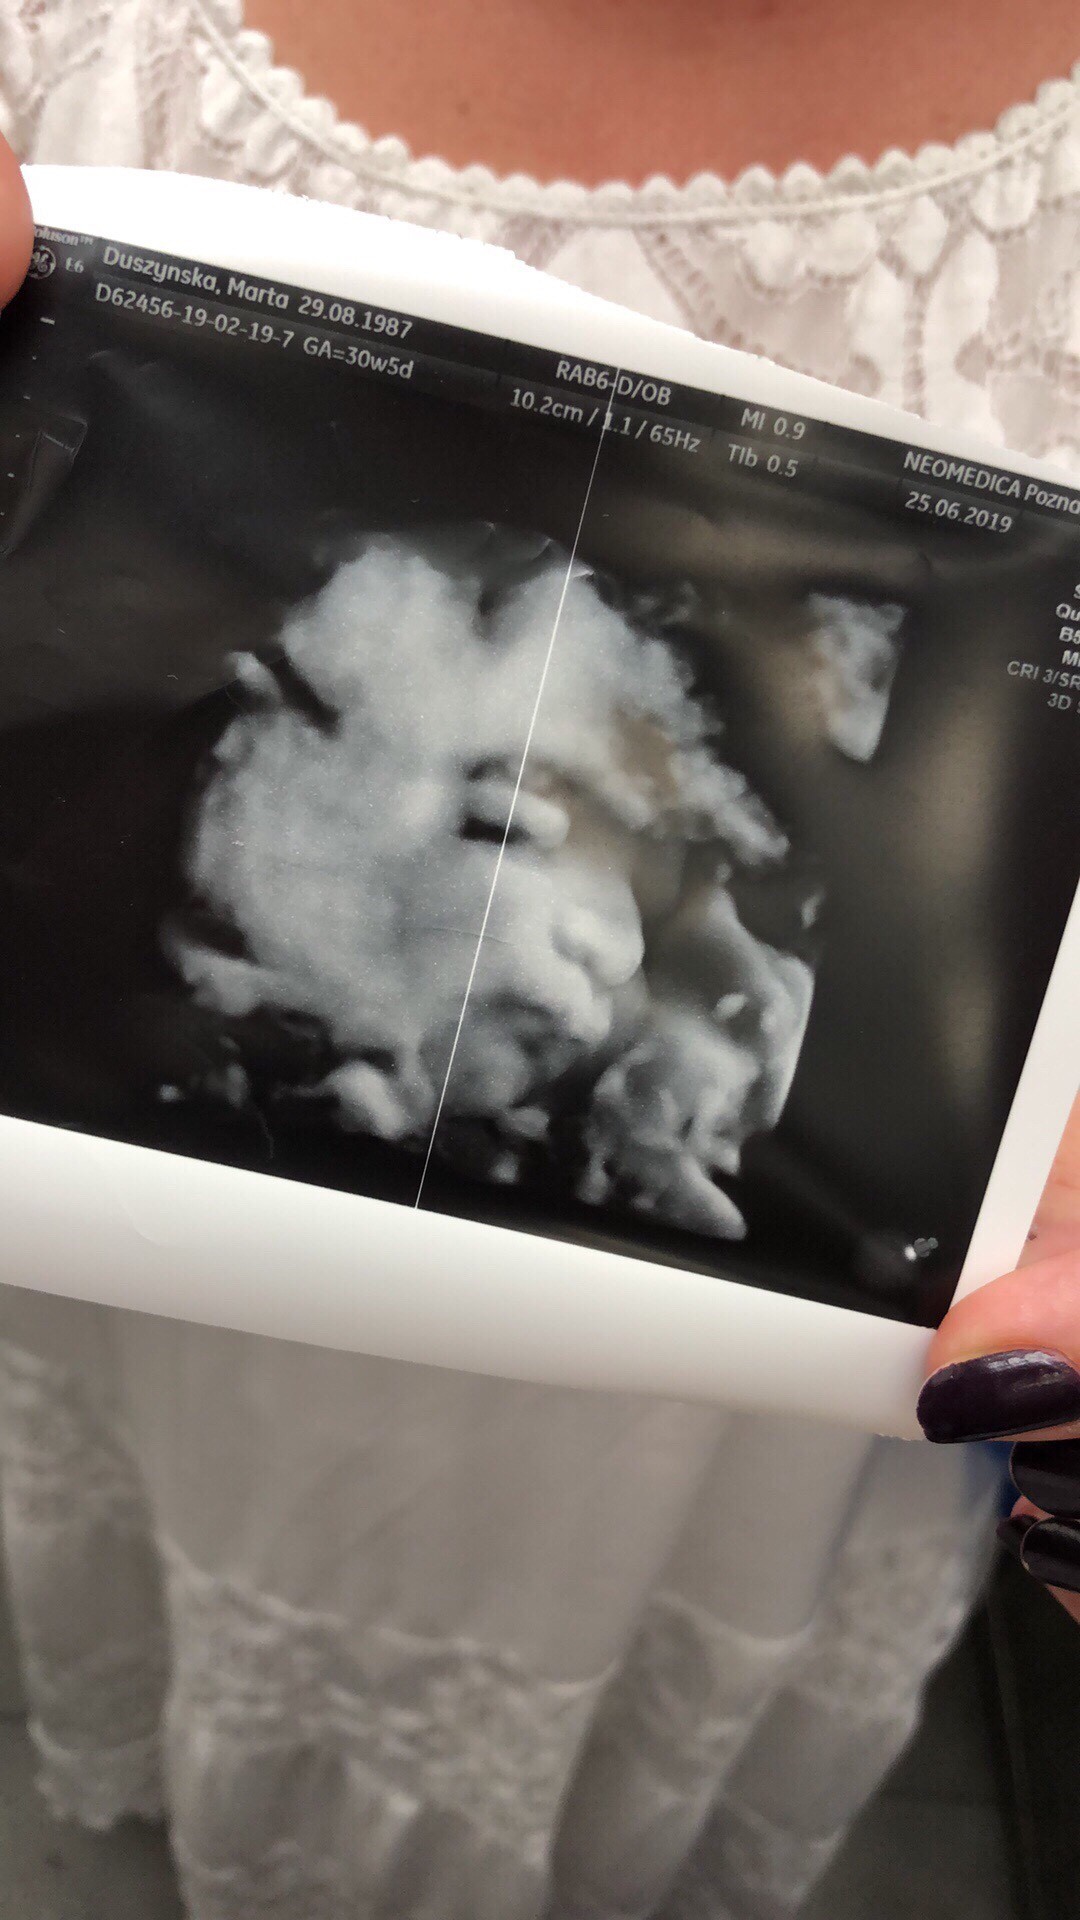

No to i ja wam sie pochwale. Moja 1612g Tosia. Zdrowa i z długimi na ponad 1,5tyg do przodu nogami [emoji173]️ jedna ze stop trzyma przy buzi. I to czym mi sie mocno wypycha to pupa [emoji23]

Zobacz załącznik 990066